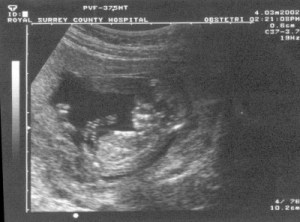

For you see, when the sound of your greeting reached my

ears, the baby leaped for joy inside me!….no wait on the news they tell me it is just a fetus.